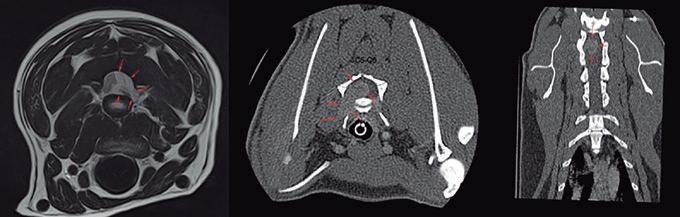

Para realizar la mayoría de los procedimientos quirúrgicos, es imprescindible disponer de un equipo de fluoroscopia, que permite la adquisición rápida de

La radiología intervencionista se realiza mediante un abordaje guiado por distintas técnicas de imagen como, por ejemplo, la ecografía, la fluoroscopia o la tomografía computarizada, para alcanzar la zona a diagnosticar o tratar.

La radiología intervencionista, también conocida como radiología vascular e intervencionista, es una especialidad que se encarga del diagnóstico y tratamiento de una gran cantidad de enfermedades de una manera mínimamente invasiva. Se realiza mediante un abordaje guiado por distintas técnicas de imagen como, por ejemplo, la ecografía, la fluoroscopia o la tomografía computarizada, para alcanzar la zona a diagnosticar o tratar.

La radiología vascular e intervencionista ofrece una alternativa segura y eficaz a la cirugía en muchas enfermedades. Entre sus ventajas para el paciente destaca una menor agresión a nivel tisular, una rápida recuperación, procedimientos sin dolor, rápidos y seguros, un menor coste respecto a otras muchas cirugías con mis-

imágenes basadas en rayos X y posteriormente las convierte en una señal de vídeo en tiempo real. Estas imágenes pueden manipularse ofreciendo funciones como la angiografía de sustracción digital, mapeo vascular y ampliación. Respecto a una radiografía, la exposición de rayos X necesaria para realizar una fluoroscopia es baja, pero debido a la duración de las series de imágenes que habitualmente se toman, el nivel de exposición en los pacientes suele ser elevado. Por lo tanto, es importante controlar el tiempo de exposición y llevar un registro de este. El fluoroscopio debe estar situado en una sala adecuada para su uso seguro, y todo el personal que entre en la sala de fluoroscopia debe protegerse de la radiación utilizando un delantal plomado, protectores de tiroides y gafas plomadas.